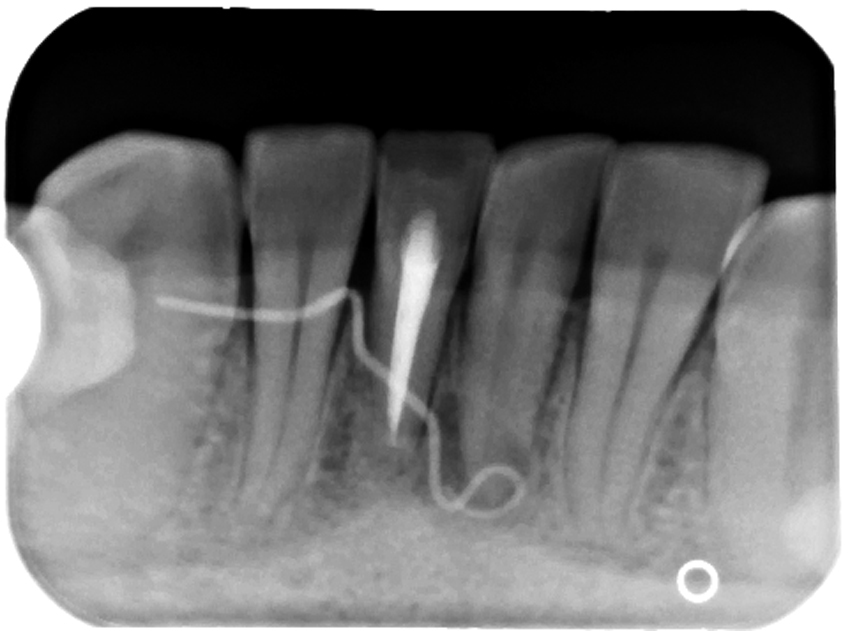

Ryc. 7. Zdjęcie zębowe zęba 31 oraz umieszczonego w przetoce ćwieka gutaperkowego. Wierzchołek ćwieka znajduje się w okolicy wierzchołka korzenia zęba 31.